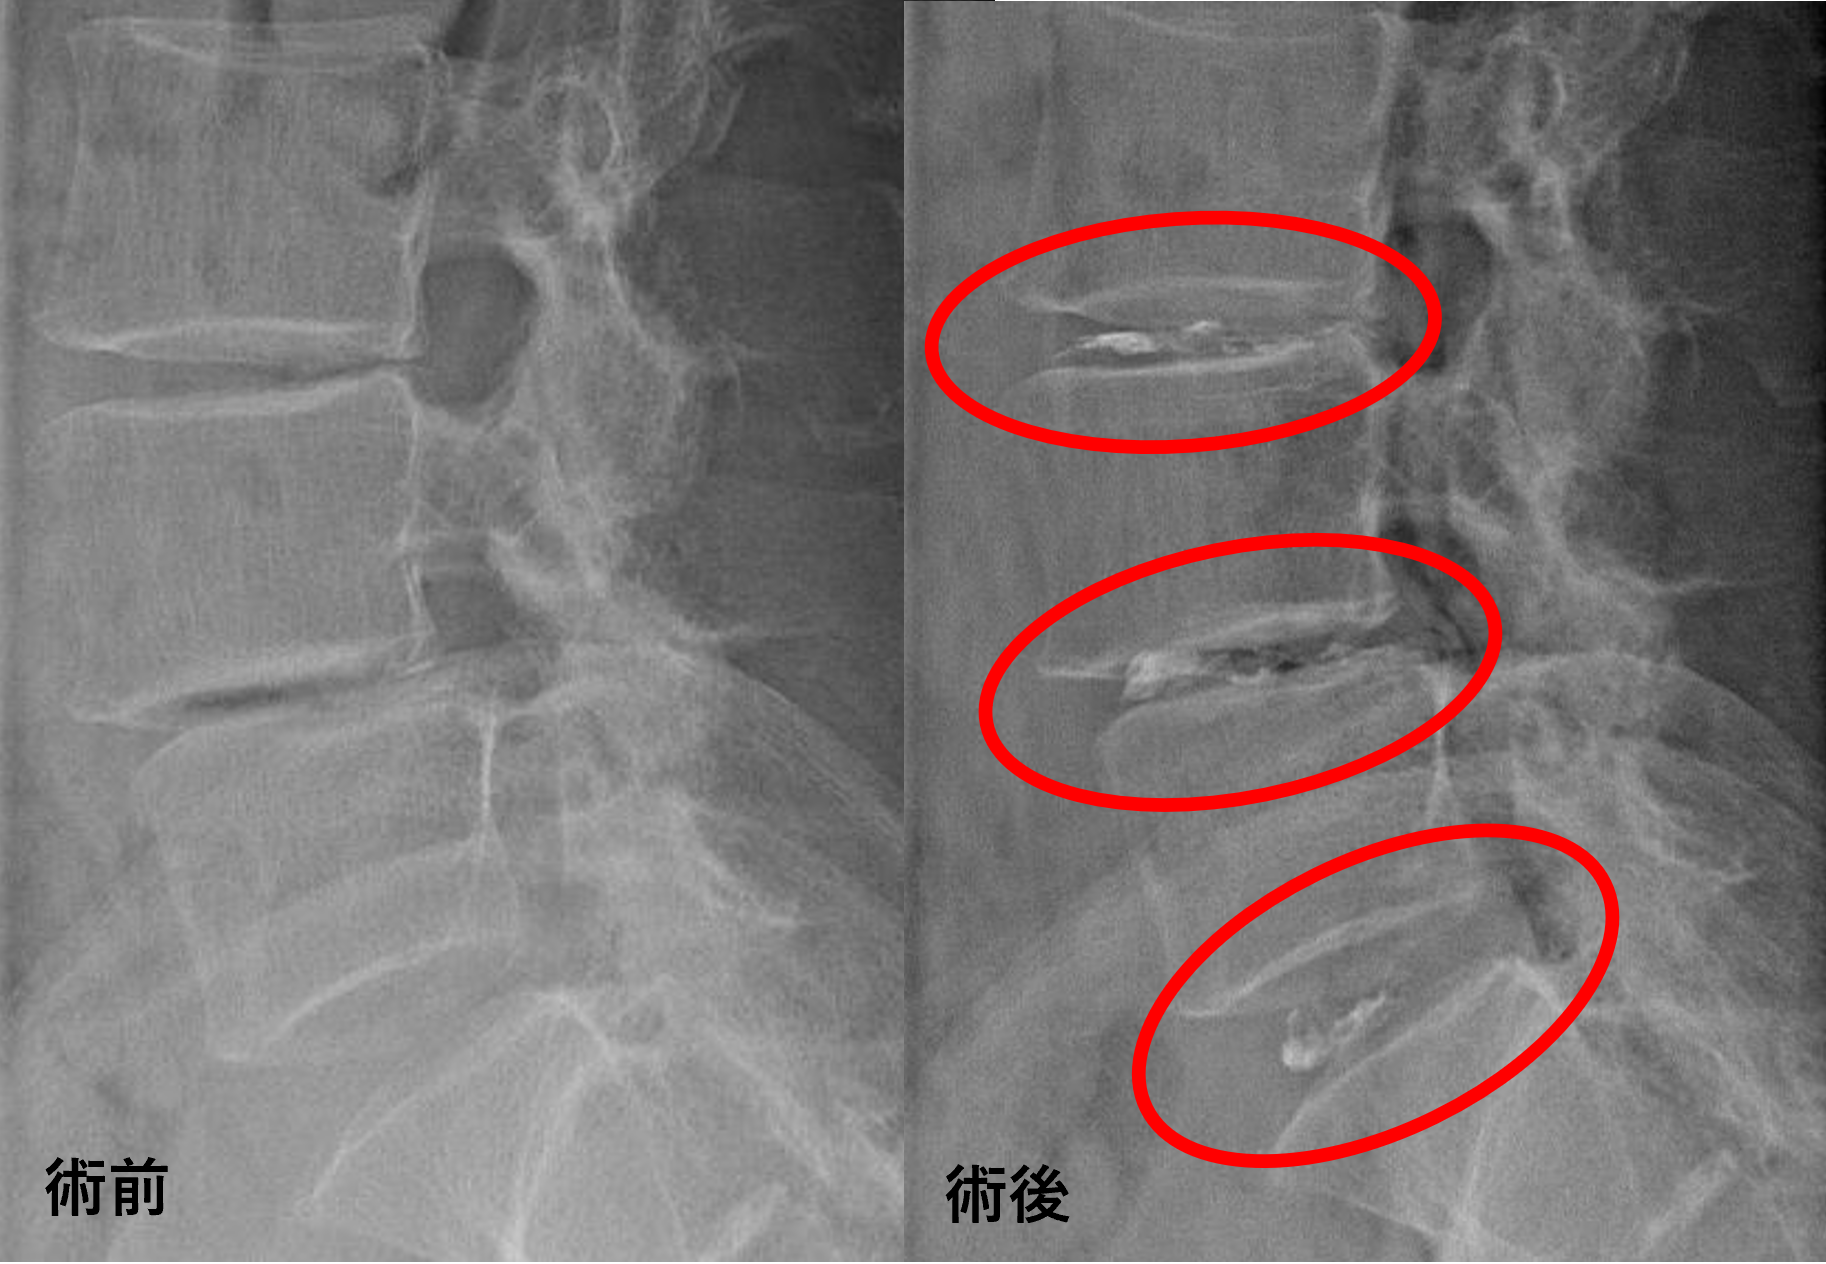

患者様と相談の元、L3/4、4/5、5/sにセルゲル法を施行

治療は25分程度で終了

回復室で休憩後、歩いて帰院されました。